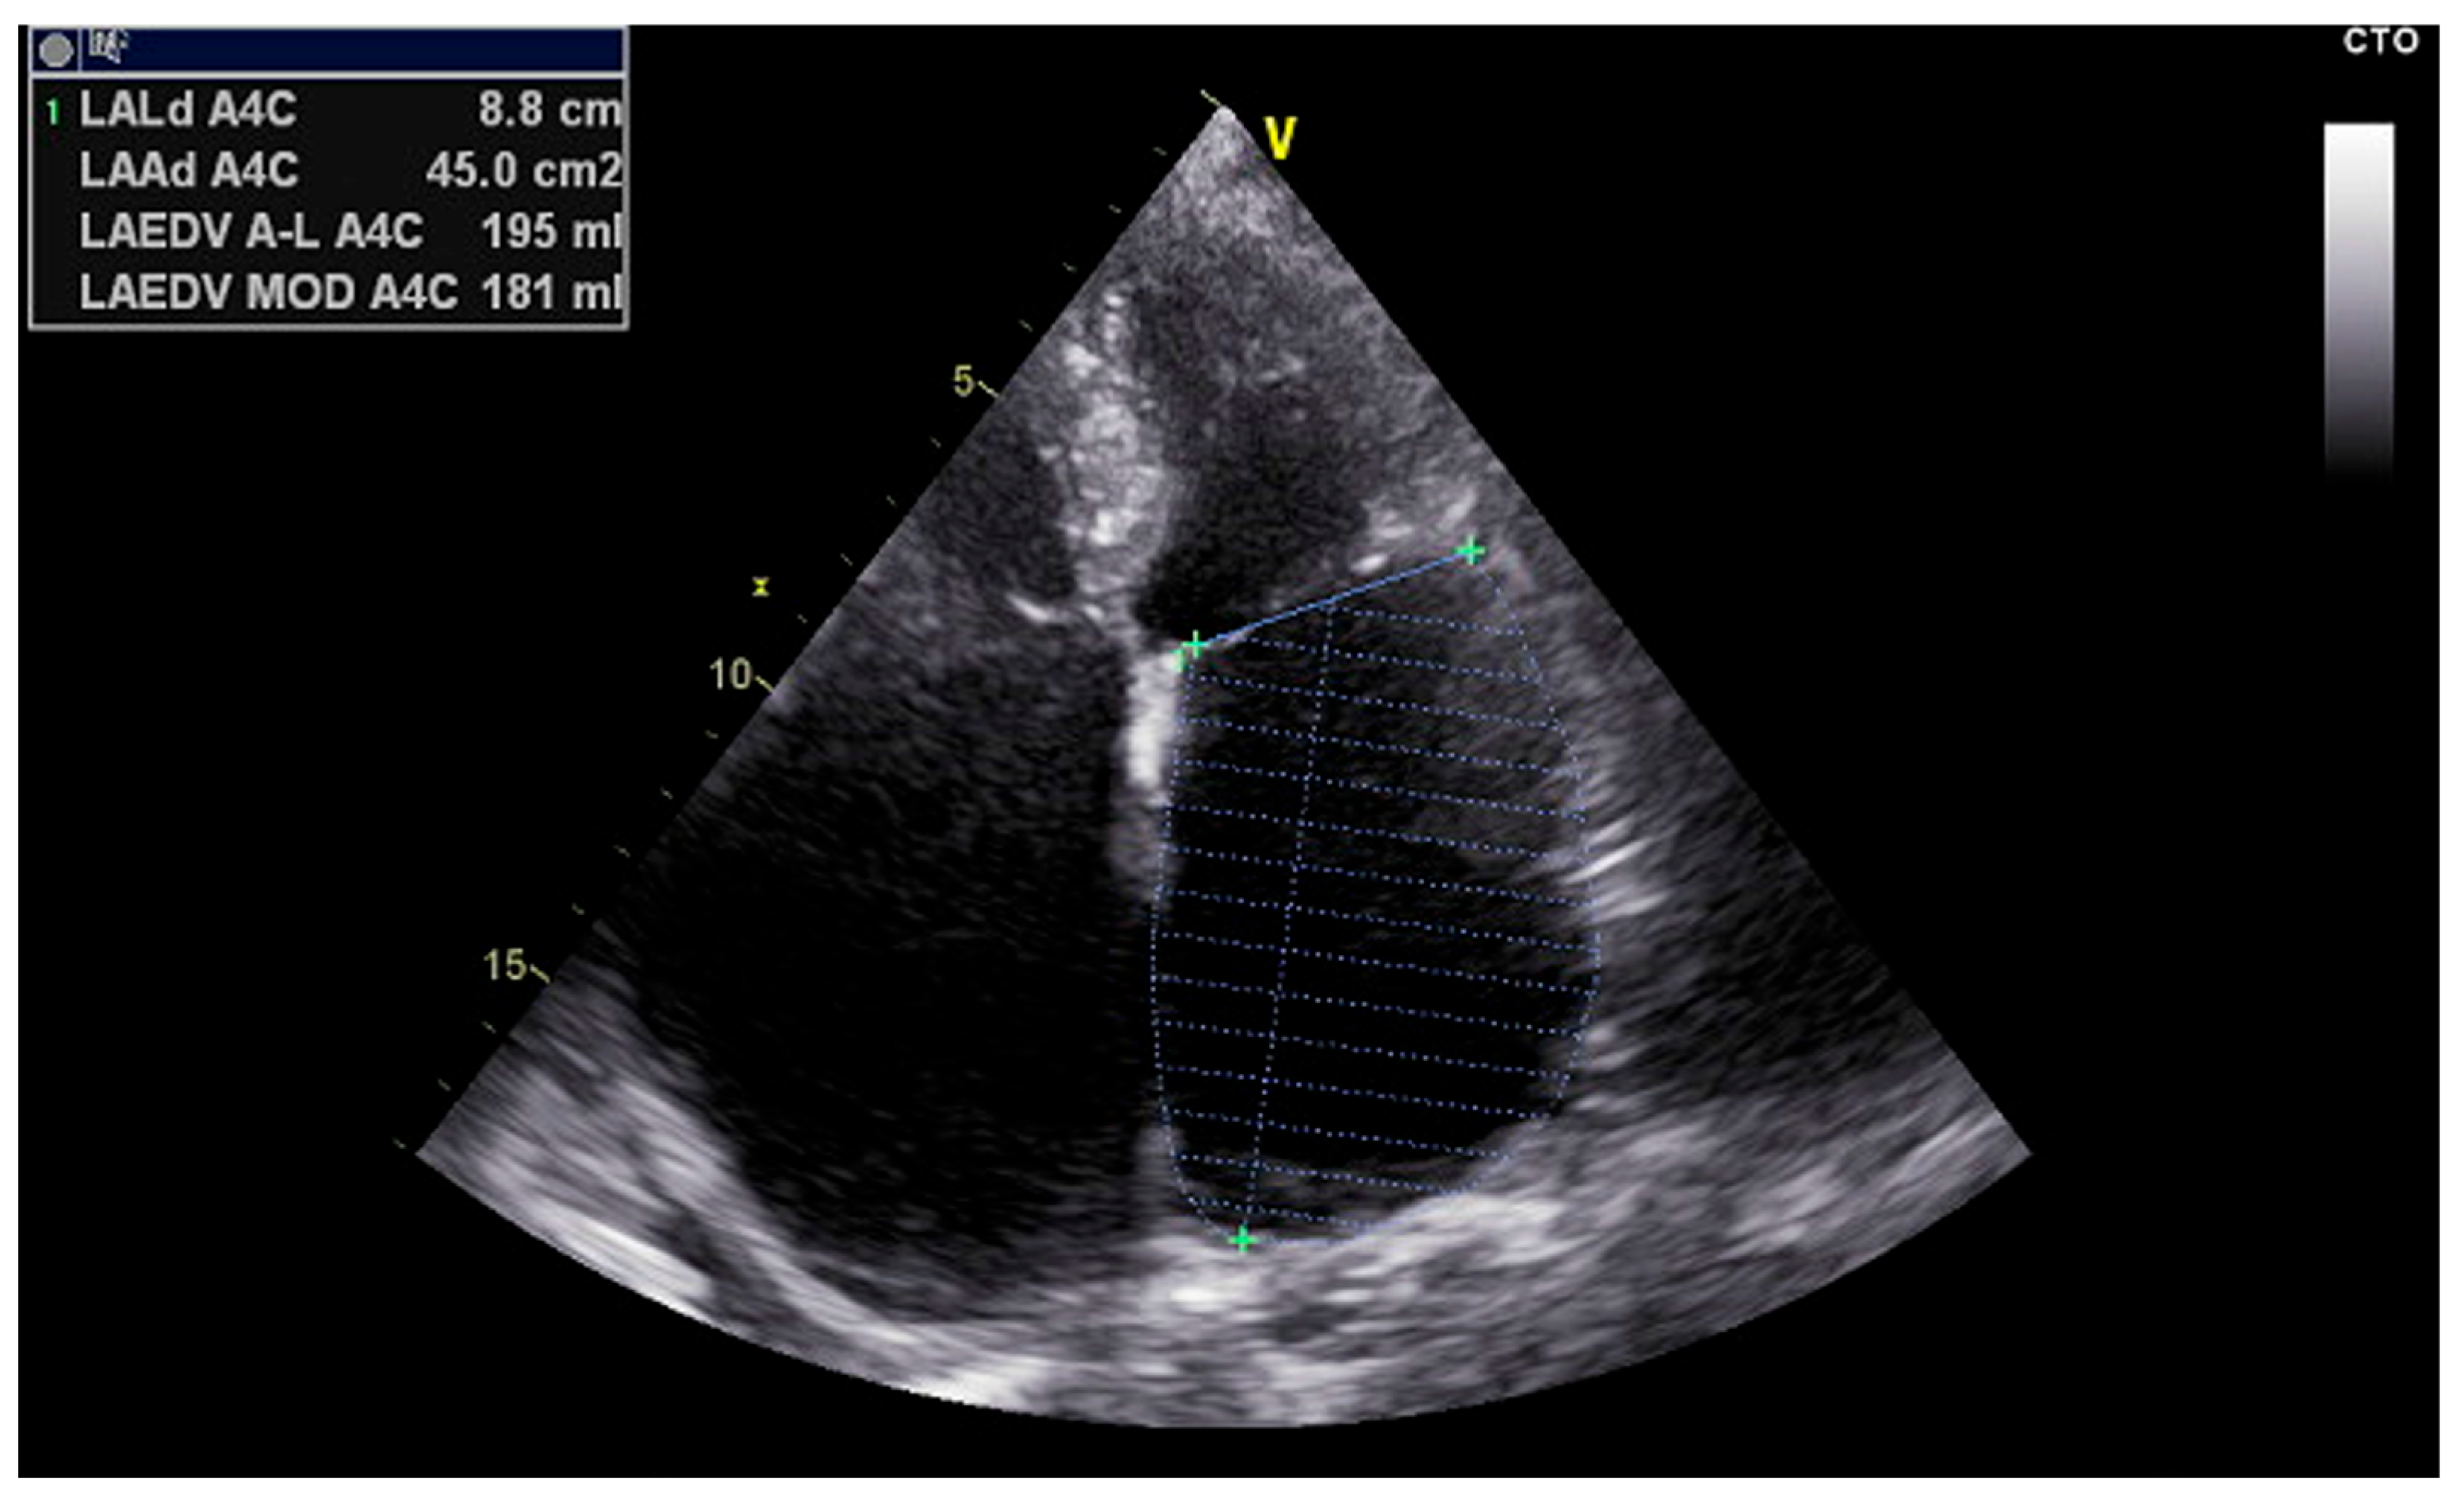

| LAVI (Volume Index) | Indicates chronic structural remodeling and LA dilation due to volume/pressure overload | Correlates with widespread CFAEs, multiple breakthrough sites, and complex activation patterns |